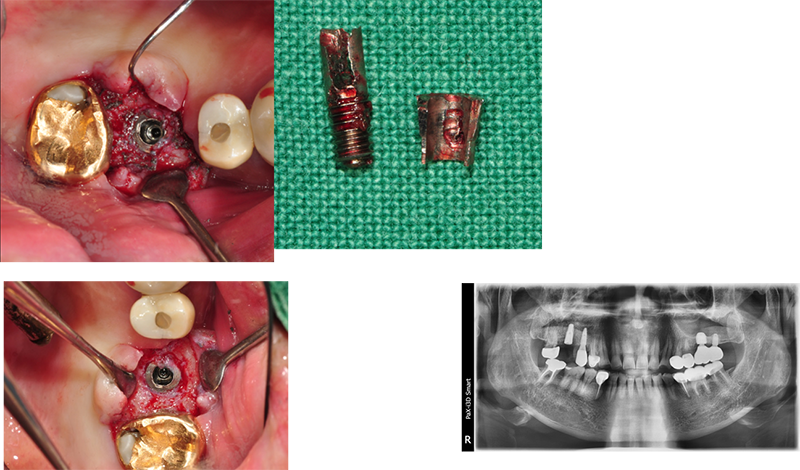

Submerged implantÀÇ ´ÜÁ¡

Wide fixture(Á÷°æ 5.5mm)

Sub typeÀº ÇȽºÃÄ Á÷°æ°ú´Â º° °³·Î ¾î¹þÀº ¸ðµÎ µ¿ÀÏÇÑ »çÀÌÁî´Ù. Ư¡ÀÌÀÚ ÀåÁ¡ÀÌ´Ù. ÇȽºÃİ¡ ºÎ·¯ÁöÁö ¾Ê¾Æ¼ ´ÙÇàÀÌ´Ù. ±×·¯³ª ¾î¹þÀÇ ¹Øµ¿ÀÌ ºÎ·¯Áø °Íµµ ¸Å¿ì Å« ÇÕº´ÁõÀÌ´Ù. ºÎ·¯Áø ¹Øµ¿À» ±ú²ýÇÏ°Ô »©³»´Â °Íµµ »ó´çÈ÷ Èûµç ÀÏÀÌ´Ù.

37¹ø 4.3 Á÷°æÀÇ ¿øÇöõÆ®

Á¦°ÅÇÏ´Ù°¡ ÈìÁýÀÌ ³¯ °Í °°¾Æ¼ Æ÷±âÇϰí

´ÙÀ½¿¡ ¾à¼Ó Àâ¾Ò´Âµ¥ ȯÀÚµµ Àúµµ ¹Ì·ç´Ù°¡ ÀÌ Áö°æµÊ.

ÆÄ³ë¶ó¸¶ »ó

°á±¹ ÇȽºÃÄ Á¦°Å

¾Æ¸¶µµ ±³ÇÕ¿¡ ¹®Á¦°¡ ÀÖ¾ú´ø µí

37¹ø abutment ÆÄÀý, µÚÂÊ¿¡ 8¹øÀÌ º¸À̰í, fixture Á÷°æÀÌ 5.0, Á¶±Ý ÈìÁýÀÌ ³ªµµ µÈ´Ù´Â »ý°¢À¸·Î Á¦°Å¼ö¼úÀ»

Çß´Ù.

3¹ø¿¡

³ª´²¼ °Ü¿ì Á¦°ÅÇÑ °æ¿ì